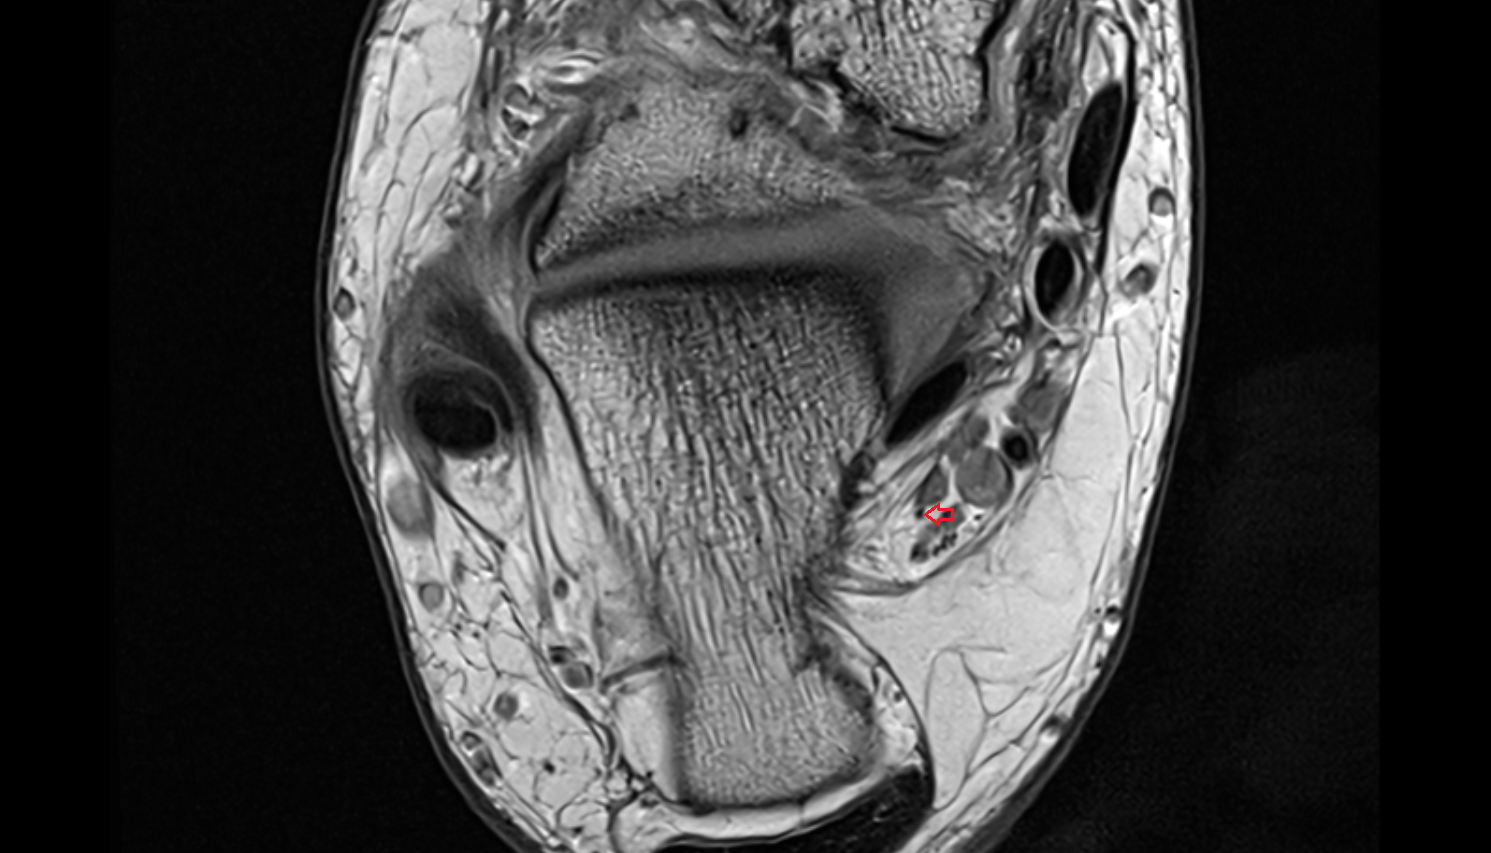

MRI images

Inferior calcaneal nerve (Baxter’s nerve) axial cross sectional anatomy 3T MRI AI enhanced radiology image-img-00000-00000_00003